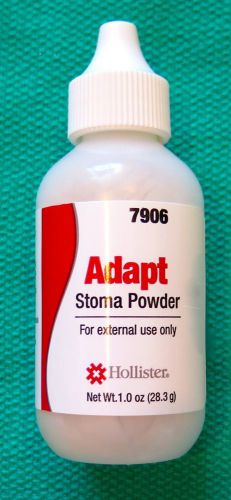

Hollister Adapt Stoma Powder 1oz-ref 7906